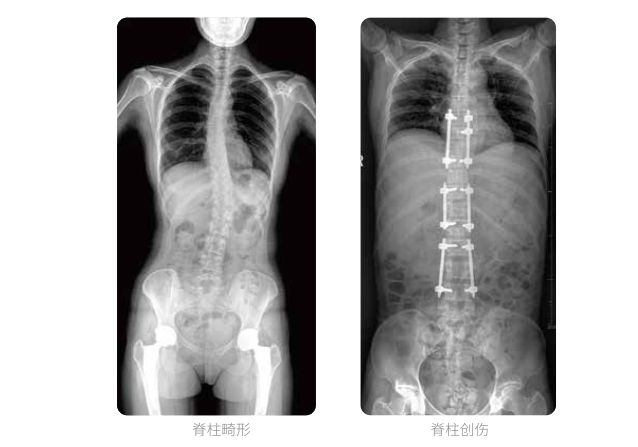

近年来,脊柱及下肢畸形的患者较多,多发于青少年的脊柱侧弯畸形,骨性关节炎、风湿性关节炎以及双下肢畸形如膝关节内外翻、X型O型腿等也是骨科常见病。并且发病率呈现逐年升高的趋势,常常累及下肢髋、膝、踝3个负重关节,影响患者生活,甚至丧失工作能力。

在脊柱及下肢畸形的临床治疗过程中,一般需要进行矫正手术治疗,在对其进行手术前后,均需要拍摄X光片以便分析病情、明确诊断和观察治疗效果。常规DR拍摄面积有限,最大规格仅有43cm,但成人男性全脊柱长度平均为70-75cm,女性为66-70cm,而双下肢更长。普爱医疗PLX8600动态DR的43cm*86cm超大有效视野,可一次性拍摄全脊柱、双下肢的影像视野。

常规DR摄片技术不能一次性拍摄出完整的全脊柱或双下肢的X光影像。全脊柱的拍摄需要分别拍摄颈椎、胸椎、腰椎的X光片,虽然能够观察到局部的侧弯情况,但不能观察到三者之间的连续性,这就增加了这类疾病的诊治难度。

普爱医疗动态数字化X线摄影(动态DR)拥有43cm*86cm超大有效视野,使全脊柱及双下肢能够得到完整清晰的成像,为临床在脊柱侧弯畸形和下肢骨关节病变诊断、治疗方案制定及治疗后复查提供精准的测量。

全脊柱临床影像

普爱医疗动态数字化X线摄影(动态DR)可以使整个脊柱一次成像,直观显示脊柱的整体形态以及侧弯部位,评价侧弯的病理程度,全面了解脊柱各个阶段的生理曲度及椎间关节连接的关系,避免了常规脊柱摄影对整个脊柱曲度的影响。为脊柱侧弯的诊断治疗提供了重要的影像学依据。